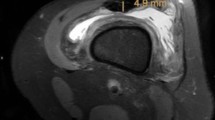

Since the QT follows an oblique course proximally and laterally, an oblique sagittal section was obtained by performing multiplanar reformation (MPR) over the high-resolution axial T1-weighted sections to determine the correct QT length. On the sagittal oblique T1-weighted images, the QT length was measured between the patella’s superior pole (patellar insertion site) and the musculotendinous junction of the rectus femoris muscle (Fig. 1). To measure the ACL length, oblique sagittal reformatted images parallel to the longitudinal axis of the ACL were created. The ACL length was measured between the midpoints of femoral and tibial attachment sites (Fig. 2).